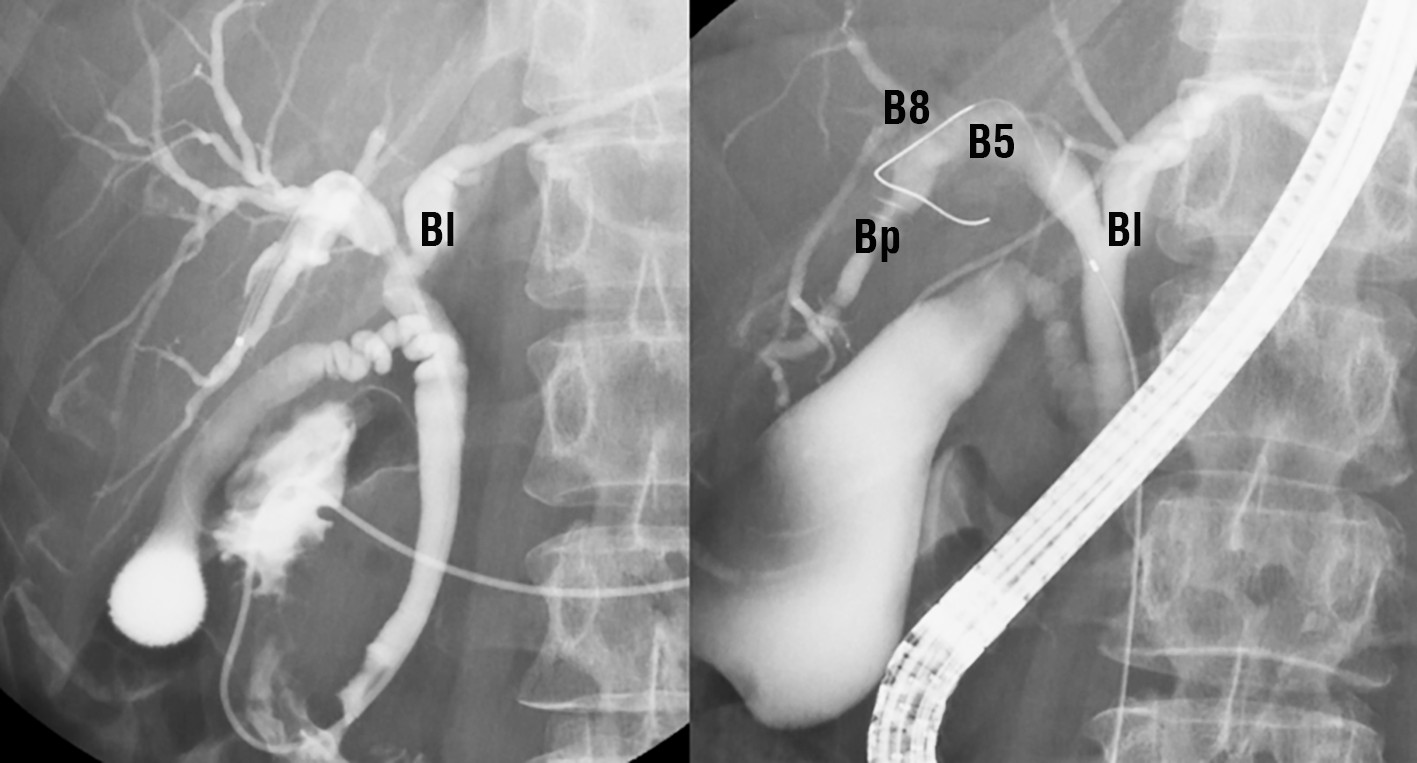

Abdominal ultrasonography identified a space-occupying lesion at liver segments 5 and 6, measuring 30 × 30 mm in diameter, with a mural nodule. Dynamic computed tomography indicated that the mural nodule inside the cyst was slightly enhanced during the early phase; this enhancement was prolonged during the delayed phase (fig. 1 a-c). Magnetic resonance cholangiopancreatography revealed that the tumor was connected to the biliary duct of segment 5 (fig. 2 a, b). Endoscopic retrograde cholangiopancreatography revealed that the intrahepatic bile duct was dilated owing to mucin produced by the tumor and that the tumor was connected to segment 5 of the biliary duct

(fig. 3). A step biopsy of the liver hilum, branches of the anterior and posterior bile ducts, and right main bile duct demonstrated no malignancy. Intraductal ultrasonography revealed an approximately 10-mm highly echogenic nodular lesion within a multifocal cyst. The nodule exhibited no intramucosal invasion of the intrahepatic bile duct (fig. 4). Therefore, IPBN was diagnosed.

Figure 3 - Endoscopic retrograde cholangiopancreatography. (a) and (b): a cystic mass traversing the biliary duct of segment 5 (B5). No bile duct anomalies are observed. The results of step biopsy and bile cytology tests are negative for the left bile duct (Bl), B8, and posterior branch of the bile duct (Bp)